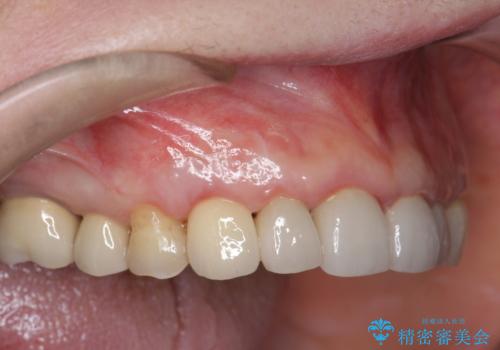

折れてしまった前歯 インプラントによる補綴治療